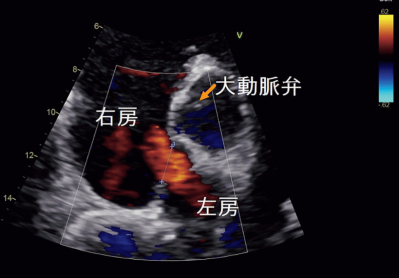

脈拍 80/分、整。血圧122/78 mmHg。SpO₂ 97 %(room air)。呼吸音に異常を認めない。経胸壁心エコー検査の傍胸骨短軸像(大動脈弁レベル)を別に示す。心臓カテーテル検査で平均肺動脈圧 30 mmHg、Qp/Qs 3.1 であった。

e. 提示した心エコー図では右房から左房への血流が認められる。